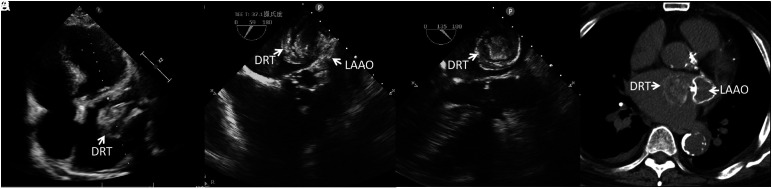

A Rare Case of a Decade-Long Device-Related Thrombus with a Unique "Tree-Ring" Structure.